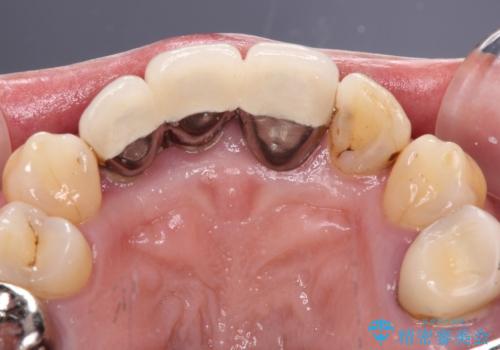

- 20年以上前に装着した前歯のメタルセラミックが不自然であることを気にして来院された患者様です。

歯肉の位置が変わり、変色した歯根が露出しているため、金属の土台をファイバーコアに交換した上で、オールセラミッククラウンにて補綴することとしました。